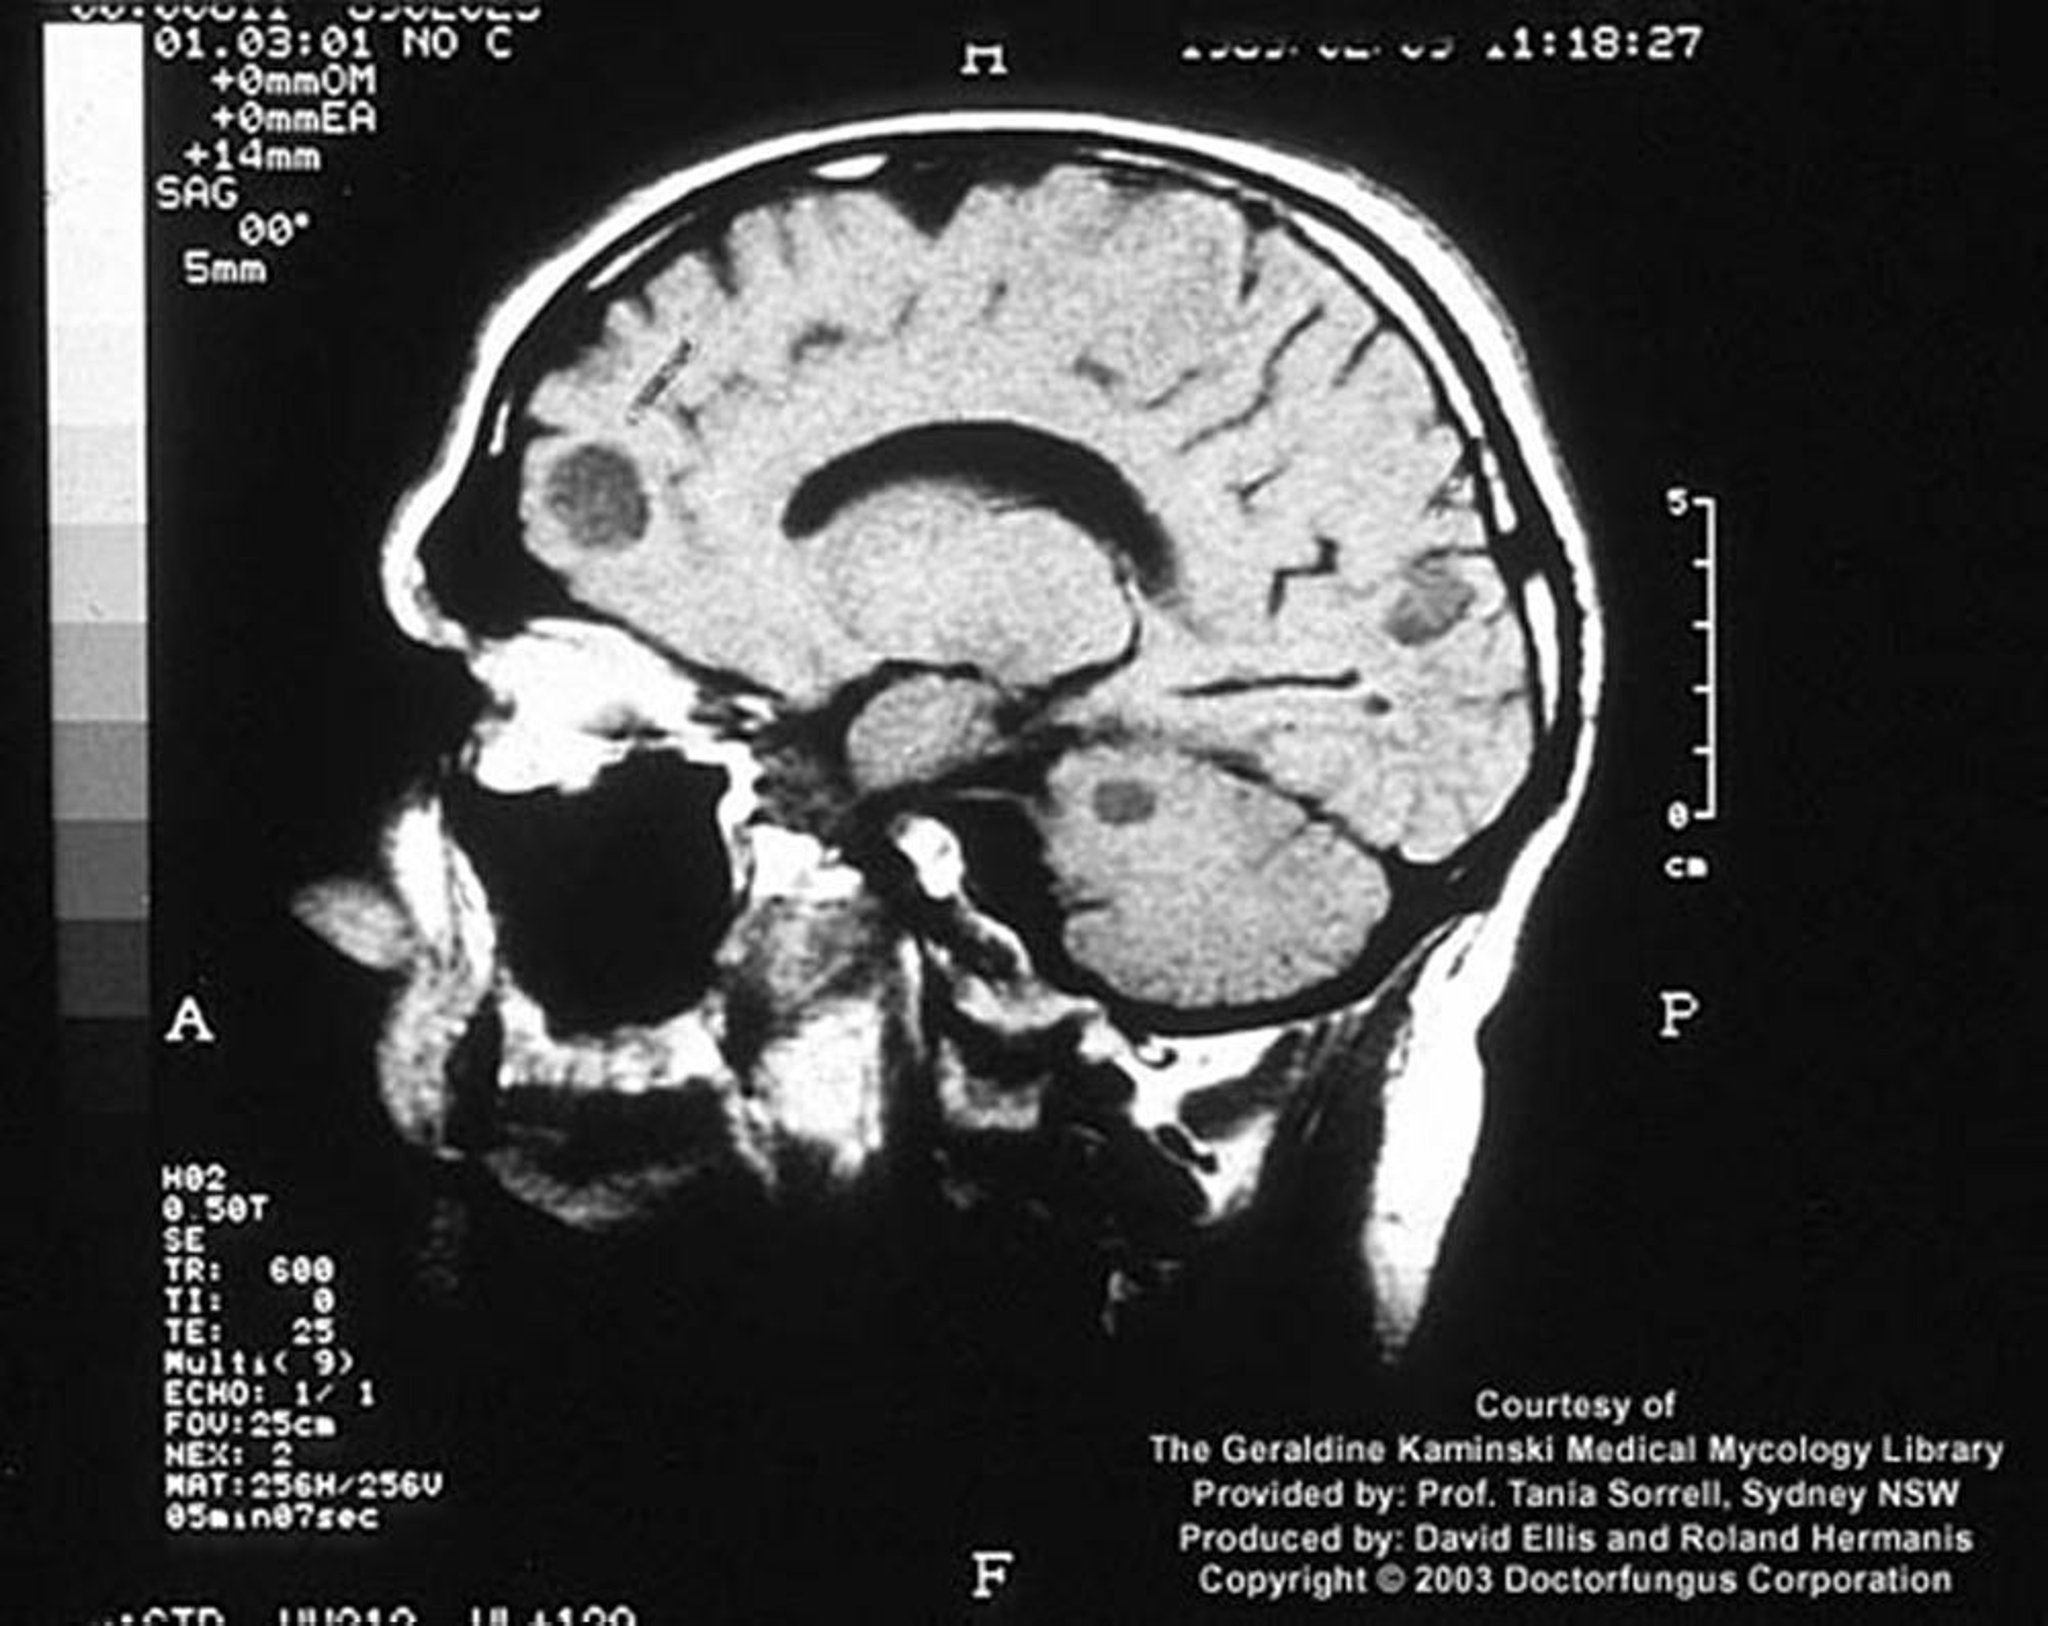

Cryptococcose (système nerveux central)

Chez un hôte immunodéprimé, l'infection cryptococcique peut se manifester par des lésions cérébrales focales appelées cryptococcomes.

Image courtoisie de www.doctorfungus.org © 2005.